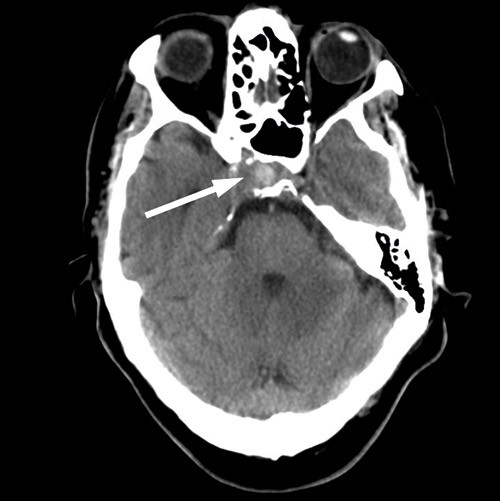

Cerebral CT og CT-angiografi like etter innleggelsen viste ikke tegn til blødning, men man fant på høyre side et intrakavernøst carotisaneurisme med diameter på 10 mm og en beineroderende prosess i sfenoidalsinus og clivus (fig 1, fig 2). MR-undersøkelse av hodet med og uten kontrast bekreftet et aneurisme i mediale del av sinus cavernosus på høyre side og beindestruksjon i samme område (fig 3).

Dagen etter transsfenoidal prøvetaking i narkose fikk pasienten akutt forverring av hodepinen, og det ble tatt en ny cerebral CT og CT-angiografi (fig 4). Den viste at den patologiske prosessen i sfenoidalsinus hadde ekspandert og at aneurismet hadde økt i størrelse til 16 mm i diameter.